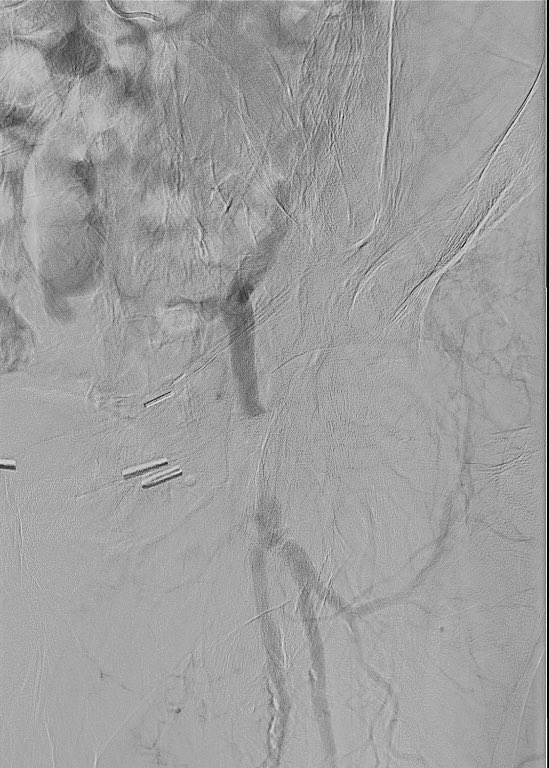

60M presents for evaluation. Runs 2 miles daily w/no symptoms and BP, lipids, A1c optimally controlled. Another doc orders a stress test given family history of CAD. 13:00 Bruce, 100% max pred HR, no symptoms, 6% rev inferior defect read as ischemia. What do you do?